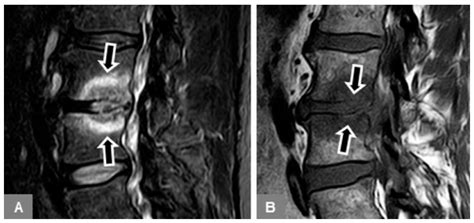

The primary reason Modic Type 1 Endplate Changes are discussed in clinical settings is their strong association with discogenic low back pain. Researchers believe that when a disc sustains a structural injury—such as a tear in the outer ring (annulus fibrosus)—pro-inflammatory chemicals from the disc core can leak into the vertebral endplate. This triggers a localized inflammatory response, leading to the bone marrow edema that characterizes Type 1 changes.

Because the vertebral endplate is richly innervated with nerves, this inflammation sensitizes these structures, resulting in persistent, deep, and often dull back pain. For many patients, this pain can become chronic and disabling, often worsening with activity or long periods of sitting.

Diagnosing Modic Type 1 Endplate Changes requires high-quality MRI imaging. Because these changes involve fluid and bone marrow, standard X-rays or CT scans are generally insufficient to see the soft-tissue-like inflammation. An MRI provides the necessary detail to differentiate between the active inflammatory state of Type 1 and the more stable, chronic states of Types 2 and 3.

Physicians will typically look for a "bright" signal on T2-weighted images and a "dark" signal on T1-weighted images at the level of the disc space. While these findings are objective, it is essential for clinicians to correlate these images with the patient's physical symptoms. In some cases, Modic changes can be found in asymptomatic individuals, so a comprehensive clinical exam is always required.